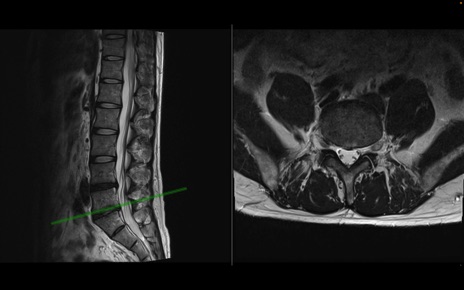

【整形】TIPS症例1 腰椎MRI 横断像と矢状断像

【症例】40歳代男性

【主訴】左臀部〜大腿後面痛み

【現病歴】2週間前から腰痛あり。2日前に夜中にくしゃみをした際に激痛が出現。疼痛強いため来院。

【身体所見】左臀部〜大腿後面、下腿後面のしびれ。SLR -/+ 30度、うつ伏せ困難、筋力低下なし。

異常所見と診断は?